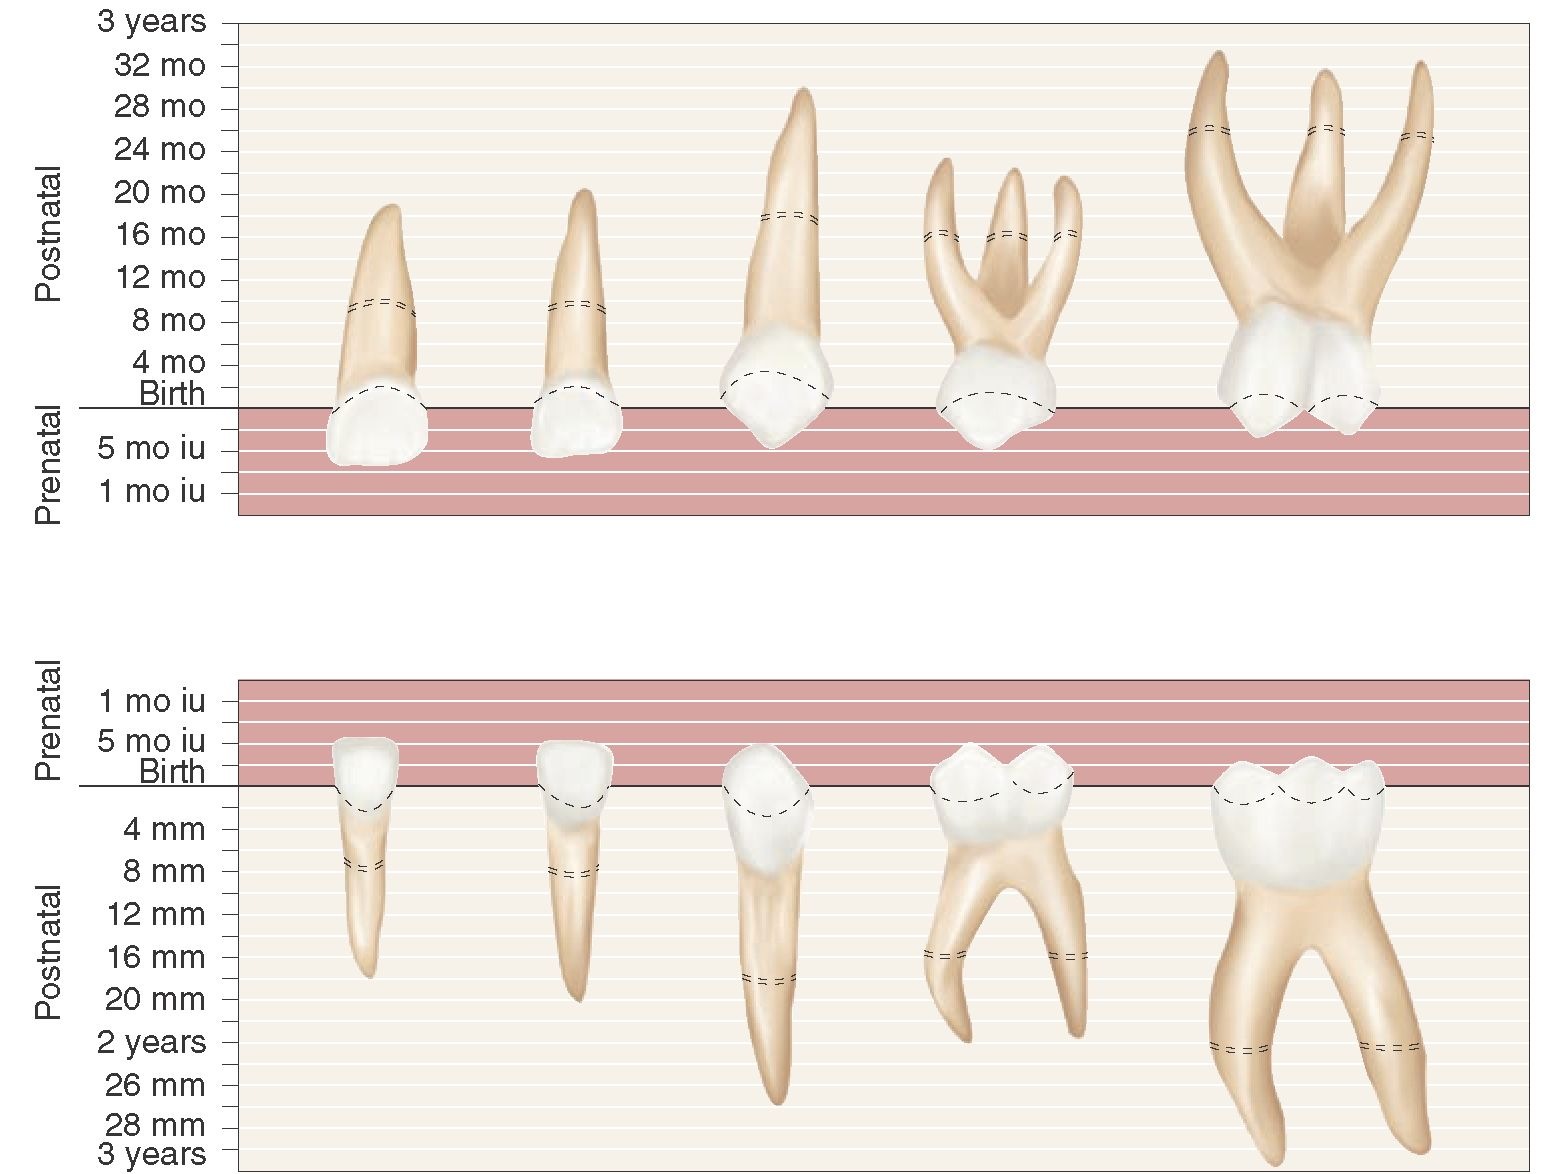

The Primary (Deciduous) Teeth (Dental Anatomy, Physiology and Occlusion

Web introduction evaluation of the eruption of mandibular third molars in orthopantomograms (opgs) is a method of forensic age assessment. Study with quizlet and memorize..

Web Introduction Evaluation Of The Eruption Of Mandibular Third Molars In Orthopantomograms (Opgs) Is A Method Of Forensic Age Assessment.